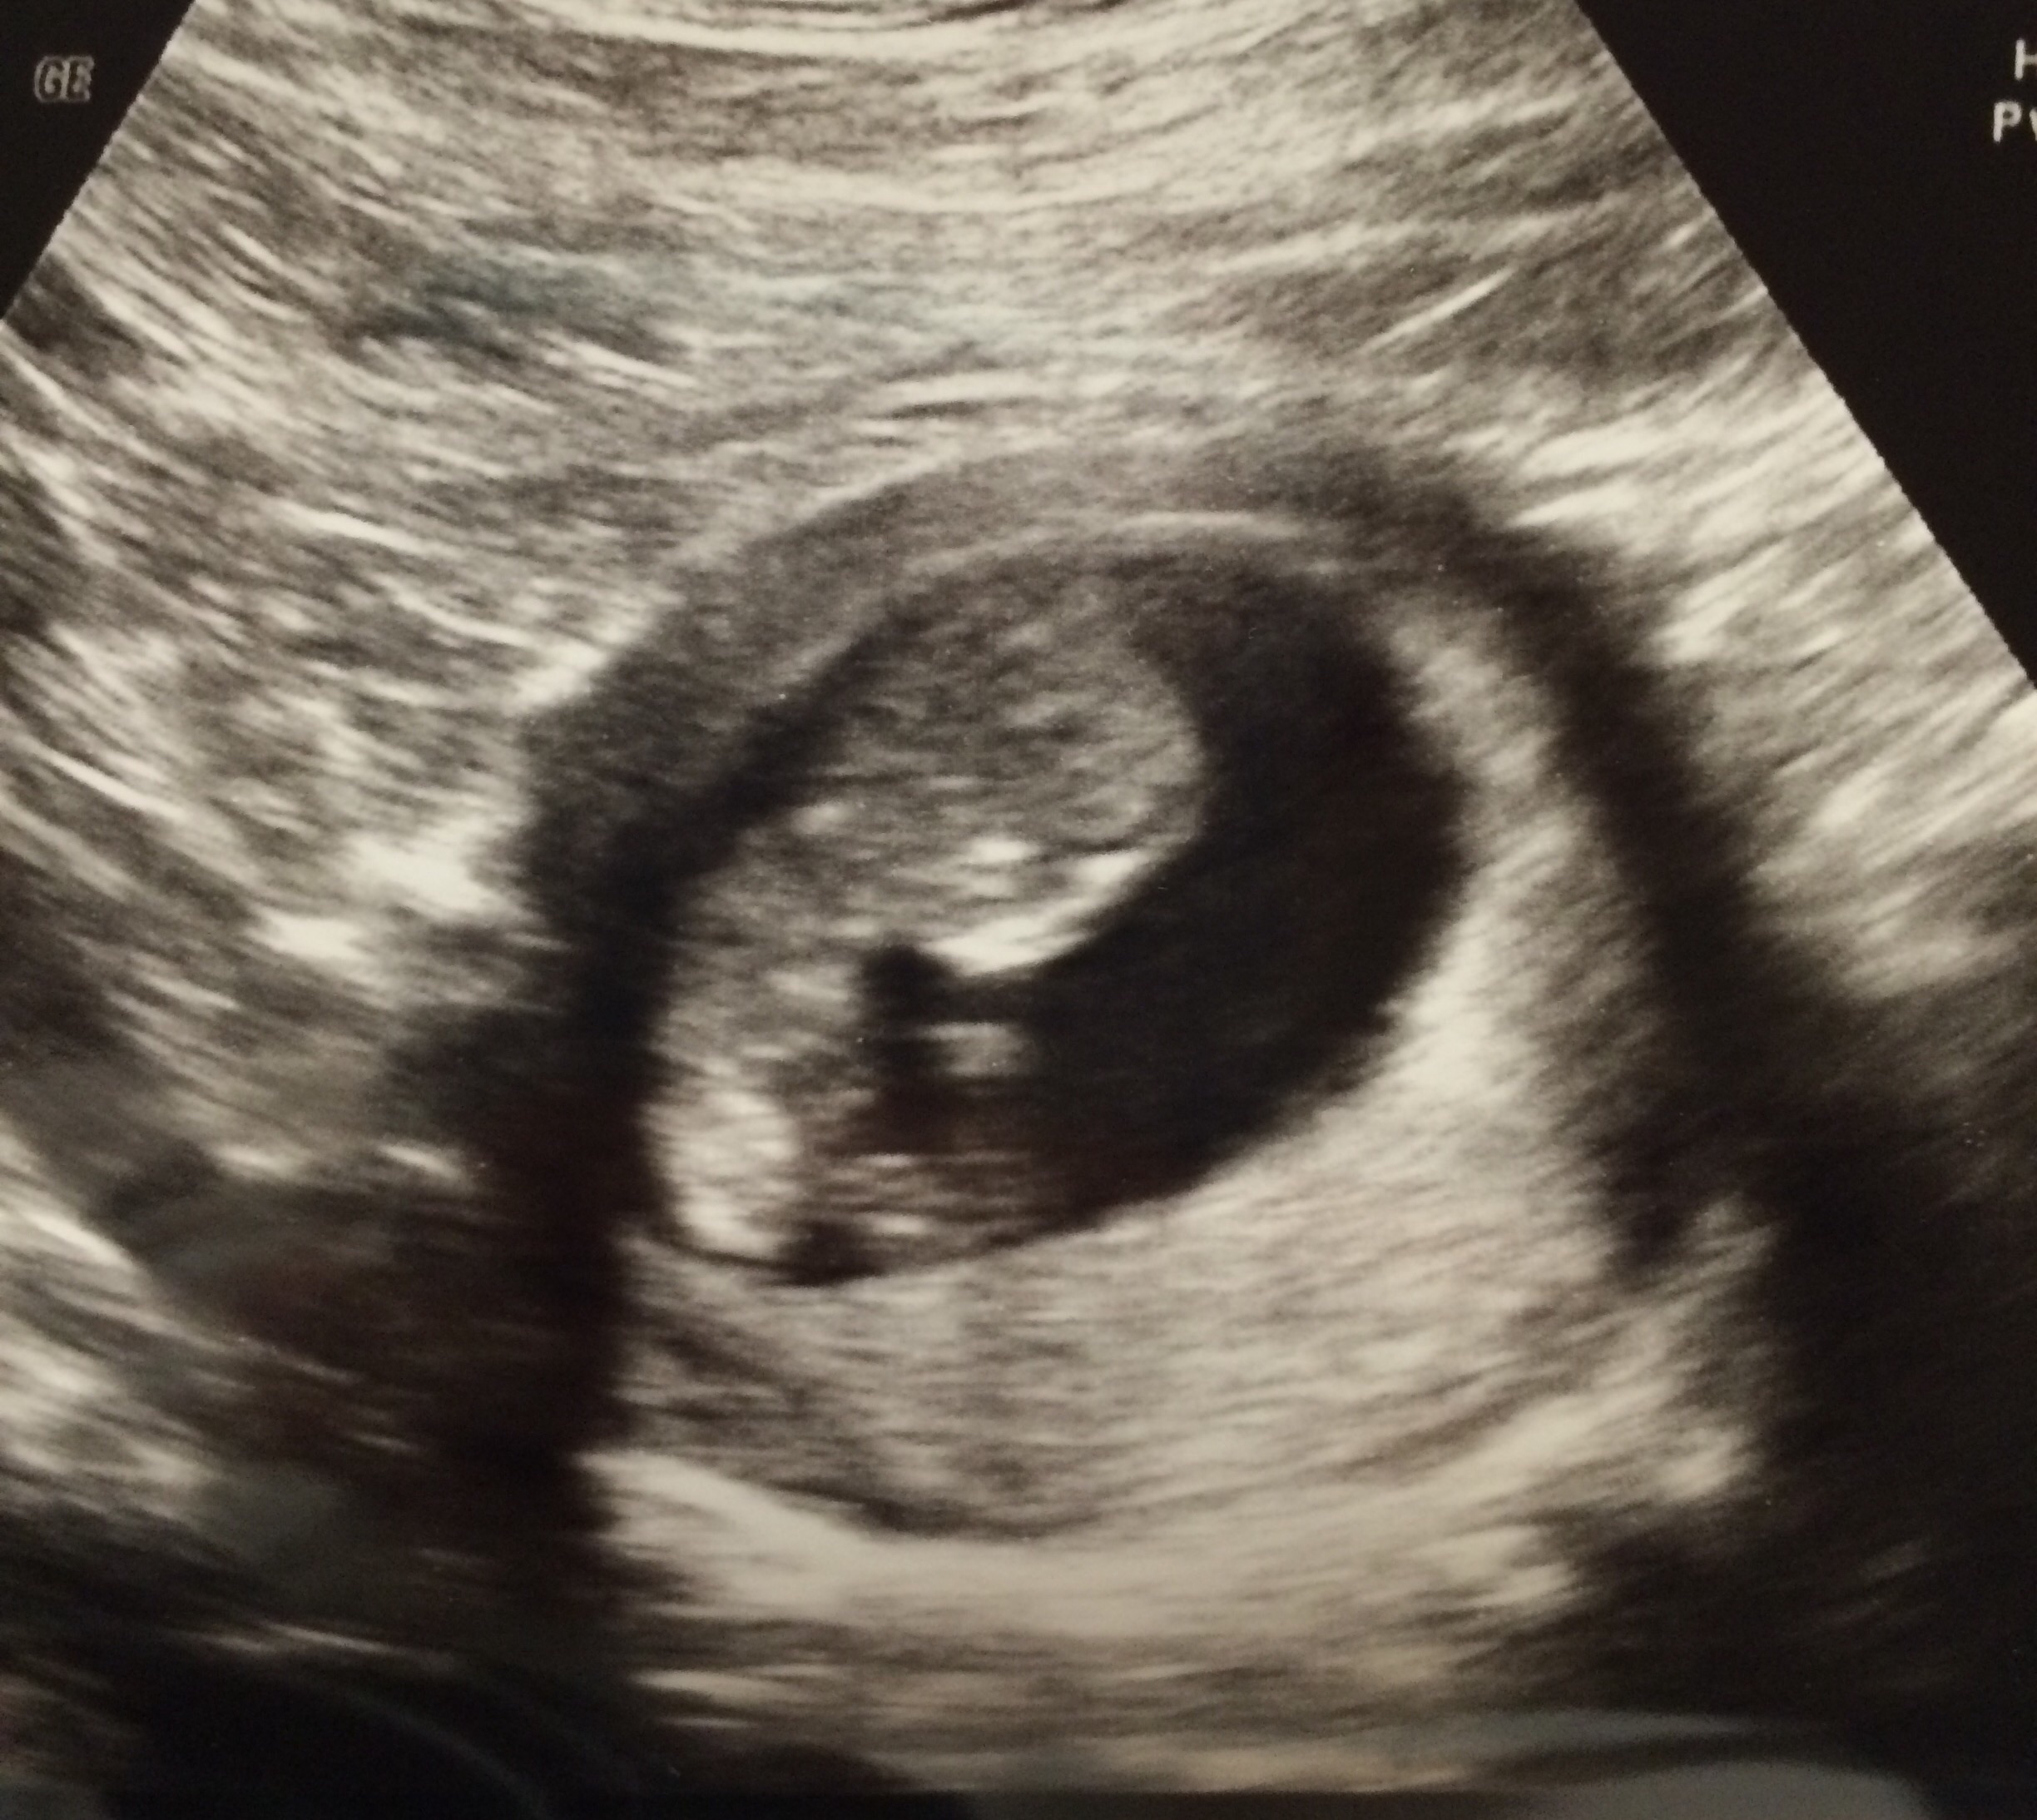

My little gummy bear about a week ago at 9w1d. We got a few pictures and I love them all, but this one I especially love because it's a front view and you can see it has its little arms folded in on its chest. Love love love!